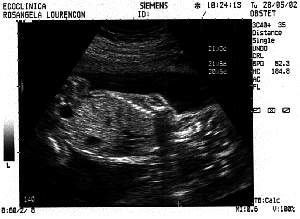

News from the "Jovem"

3rd Session - 28th May 2002

Week: 21

Size: Around

25 cm

Obs: IT'S A BOY !

Look this head. A genius :)

Laid back, hangin in there.